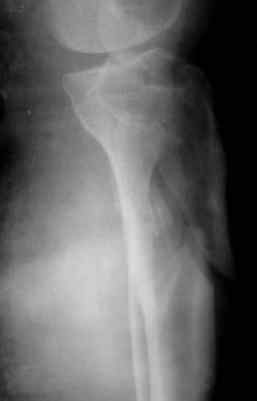

Мама 4 дня назад получила двойной перелом в голени

Диагноз такой:

1) Открытый перелом нижней 3-й большой берцовой кости

2) Верхней 3-й малой берцовой кости справа со смещением

Снимки смогли сделать только через 4 дня, я смогла приложить только 1 снимок к форуму

В пятку ей вставили штырь и повесили гирю сразу.